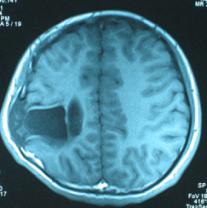

頭顱CT和MRI可見顱骨缺損區(qū)下方軟腦膜囊腫、腦軟化灶或腦室穿通畸形(圖2)。

圖2:①和②CT及骨窗相顯示右頂部顱骨缺損,其下方腦組織呈低密度改變;③-⑥MRI右頂局部顱骨缺如,腦組織輕度向外膨隆,右頂葉側(cè)腦室體部旁局部腦組織缺如,代之以囊性長T1、長T2信號。